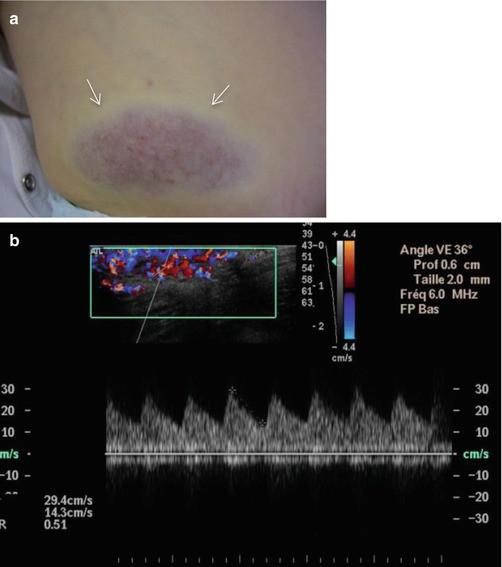

Congential hemangioma in a 3-year-old boy. (a) Clinical photograph. (b) Axial color Doppler image with spectral display obtained in tumor center. (a) Non-involuting congenital hemangioma (NICH) is seen as an overlying bluish discoloration with clear peripheral halo (arrow). The lesion has been present since birth, growing proportionally to the patient’s growth. (b) Color Doppler image shows the marked increased vascularity inside the lesion with low-resistance arteries. The imaging features are indistinguishable from those of infantile hemangioma

Angiosarcoma in a 70-year-old men. (a) Clinical photograph. (b) Axial color Doppler image. (c) Computed tomography. (a) Clinical appearance of numerous skin lesions. (b) Ultrasound with color Doppler shows nodular superficial tissue mass, slightly hypoechogenic and predominately peripheral flow within the soft tissue mass. (c) Computed tomography demonstrates a non specific subcutaneous nodular lesion